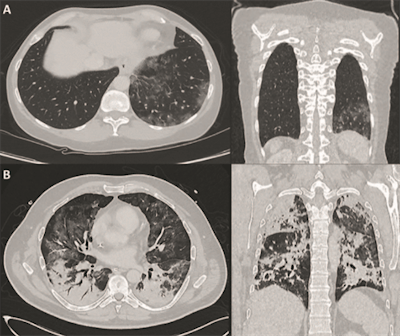

CT images of two patients with COVID-19 pulmonary manifestations. Incidental finding of SARS-CoV-2 infection in an asymptomatic 60-year old female (A) show peripheral ground-glass opacities in basal segments of the right lung. A polymerase chain reaction test confirmed SARS-CoV-2 infection on molecular level. A 51-year-old SARS-CoV-2-positive male (B) with pronounced bilateral pulmonary involvement of COVID-19 was hospitalized in an intensive care unit. Typical lesion spread to the center of the lungs and consolidation is present. Images courtesy of Nuklearmedizin.FDG uptake patterns in other parts of a patient's body also can be attributed to COVID-19, which is known to damage the heart, kidneys, or bone marrow. Hence, whole-body PET could be used as a "noninvasive readout to assess [chronic] and concomitant organ damage," the authors wrote, citing a March 2020 report by Zou et al, which found FDG uptake in the bone marrow of one COVID-19 patient (Radiology, March 6, 2020).